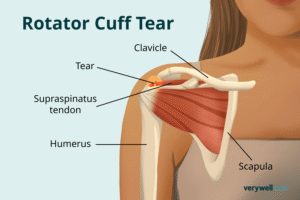

Rotator Cuff Tear

Damage to shoulder tendons causing pain and weakness.